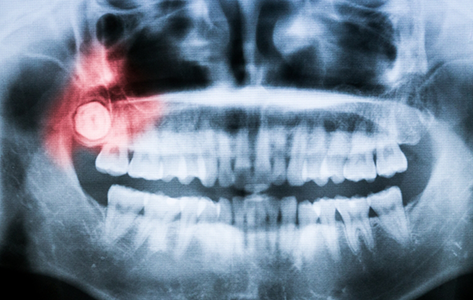

X ray of mouth with wisdom teeth highlighted

Wisdom teeth are also known as third molars, and these teeth were once essential to maintaining a healthy diet. Early human civilizations consumed dense game and uncooked vegetables and roots – foods that required the gnawing power of these teeth. Over time, though, diets changed, resulting in the narrowing of facial structures. As this happened, there became less available space for these molars to erupt – a problem that frequently causes partial eruption or impaction.